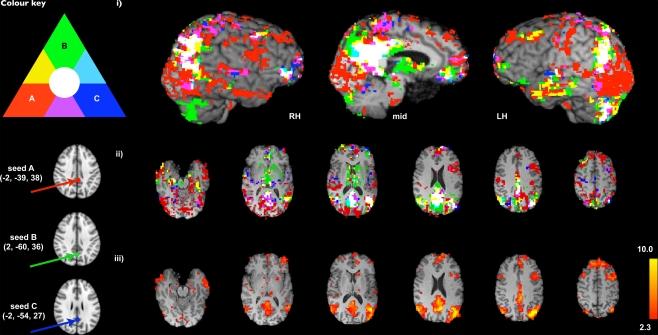

The last 15 years have witnessed a steady increase in the number of resting-state functional neuroimaging studies. The connectivity patterns of multiple functional, distributed, large-scale networks of brain dynamics have been recognised for their potential as useful tools in the domain of systems and other neurosciences. The application of functional connectivity methods to areas such as cognitive psychology, clinical diagnosis and treatment progression has yielded promising preliminary results, but is yet to be fully realised. This is due, in part, to an array of methodological and interpretative issues that remain to be resolved. We here present a review of the methods most commonly applied in this rapidly advancing field, such as seed-based correlation analysis and independent component analysis, along with examples of their use at the individual subject and group analysis levels and a discussion of practical and theoretical issues arising from this data 'explosion'. We describe the similarities and differences across these varied statistical approaches to processing resting-state functional magnetic resonance imaging signals, and conclude that further technical optimisation and experimental refinement is required in order to fully delineate and characterise the gross complexity of the human neural functional architecture.

过去 15 年见证了静息态功能神经影像学研究数量的稳步增加。多个功能、分布式、大规模脑动力学网络的连接模式已被认为是系统和其他神经科学领域的有用工具。功能连接方法在认知心理学、临床诊断和治疗进展等领域的应用已经取得了有希望的初步结果,但尚未完全实现。这部分是由于仍有待解决的一系列方法学和解释性问题。在这里,我们回顾了该领域中最常用的方法,如基于种子的相关分析和独立成分分析,并举例说明了它们在个体和组分析水平上的应用,以及讨论了从这些数据“爆炸”中产生的实际和理论问题。我们描述了这些处理静息态功能磁共振成像信号的不同统计方法之间的相似性和差异,并得出结论,需要进一步进行技术优化和实验改进,以充分描绘和描述人类神经功能结构的总体复杂性。